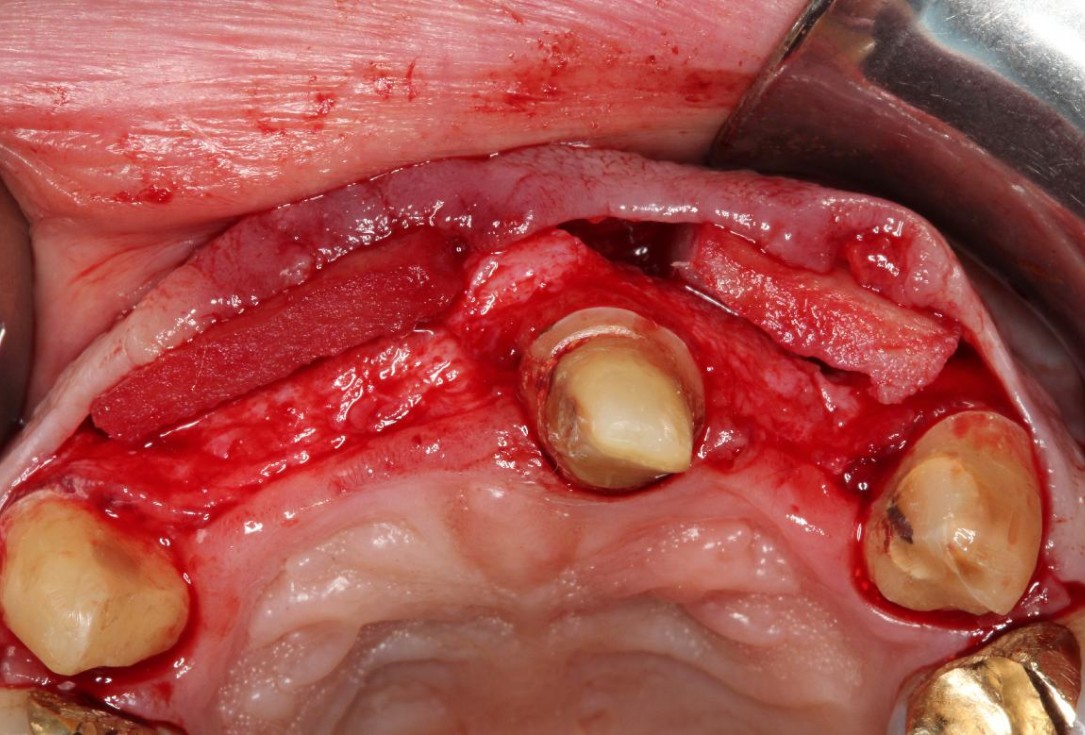

2/5 - Split-thickness flap preparation (except regio 21)Pre-prosthetic soft tissue augmentation of the ridge contour with mucoderm®- Dr. F. Rathe

Full-thickness flap preparation bucally and lingually